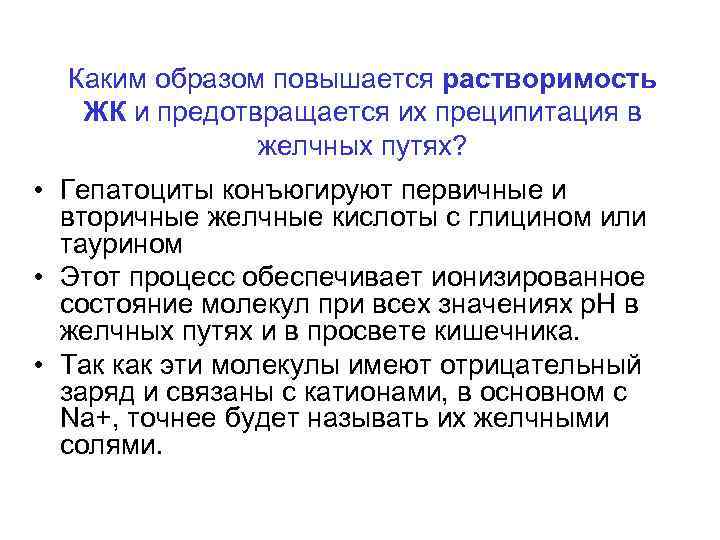

Каким образом повышается растворимость ЖК и предотвращается их преципитация в желчных путях? • Гепатоциты конъюгируют первичные и вторичные желчные кислоты с глицином или таурином • Этот процесс обеспечивает ионизированное состояние молекул при всех значениях р. Н в желчных путях и в просвете кишечника. • Так как эти молекулы имеют отрицательный заряд и связаны с катионами, в основном с Na+, точнее будет называть их желчными солями.

Каким образом повышается растворимость ЖК и предотвращается их преципитация в желчных путях? • Гепатоциты конъюгируют первичные и вторичные желчные кислоты с глицином или таурином • Этот процесс обеспечивает ионизированное состояние молекул при всех значениях р. Н в желчных путях и в просвете кишечника. • Так как эти молекулы имеют отрицательный заряд и связаны с катионами, в основном с Na+, точнее будет называть их желчными солями.